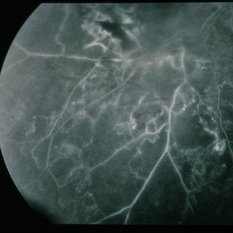

BRVO - Massive Exudate from Collaterals

Feb 24 2014 by David Callanan, MD

66-year-old female with BRVO - massive exudate from collaterals, 20/70 OD; 20/25 OS in 1985; +HTN, glaucoma; 20/200 OD 1987.

Condition/keywords: branch retinal vein occlusion (BRVO), collaterals, exudate